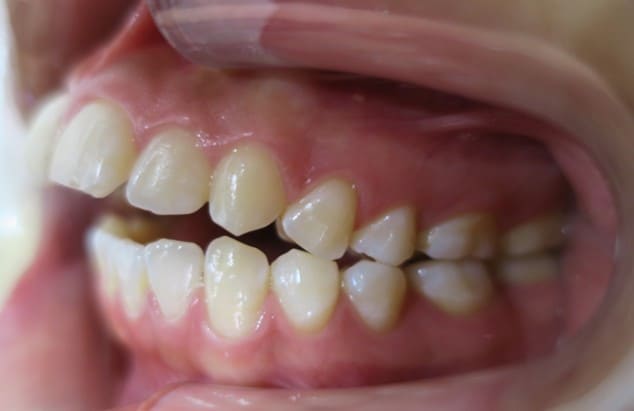

● 歯根が折れ保存不可の歯を抜歯して、そのスペースに八重歯を並べた症例

藤沢デンタルオフィスの虫歯や破折で抜歯後の部分矯正